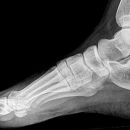

Fuß streng seitlich

Komplexe anatomische Verhältnisse => Zusätzlich a.p.- und schräge Aufnahme oder Vergleichsaufnahmen der Gegenseite anfertigen! Komplexen Luxationen/ Frakturen => großzügige CT-Indikation! Zentrale Kalkaneusfrakturen (vgl. Kalkaneus) => absolute CT-Indikation! Isolierte Frakturen des Os naviculare, der Ossa cuneiforma oder des Cuboids sind Raritäten => Immer nach zusätzlichen Verletzungen (Calcaneus, Talus, OSG,...) suchen!

Beurteilungskriterien

- Korrekte Stellung, kongruente Gelenkflächen?

- Klassisches Zeichen zentraler Kalkaneusfrakturen in der seitlichen Aufnahme: Abflachung des BÖHLER- Tubergelenkwinkels, physiologisch 25-40° (vgl. Kalkaneus seitlich)

- "target areas" subtiler Frakturen: Talushals, Proc.posterior tali, Proc.lateralis tali, Proc.ant.calcanei, Sustentaculum, Entenschnabelfraktur (knöcherner Ausriß des Ansatzes der Achilllessehne), Tuberositas ossis metatarsalis V!!!

Cave:

- akzessorische Knochen und Normvarianten der Apophsenentwicklung Wachstumsalter (vgl. a.p.-Aufnahme)

- Ermüdungsfrakturen initial oft nicht erkennbar => Röntgenkontrolle in 8-10d.